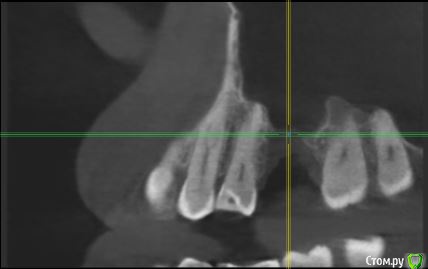

Федор С Опубликовано 1 февраля, 2018 Поделиться Опубликовано 1 февраля, 2018 Здравствуйте!Подскажите, пожалуйста, как лучше поступить в моей ситуации. Предыстория такова: из-за некачественно сделанной в свое время коронки, под верхней правой шестеркой образовалась киста. После грубого удаления зуба, образовалась большая дырка.Вопрос в следующем: ставить мост или попытаться нарастить костную ткань и поставить имплант?Сам больше склоняюсь к имплантации, но смущает, что дефект очень большой, в объеме около одно кубического см.Фото прикладываю, так же на всякий случай прикладываю ссылку на КТ (КТ делал в "Пикассо") КТ только папка DATA с диска - http://fayloobmennik.cloud/7187773Если не будет открываться, КТ весь диск целиком - http://fayloobmennik.cloud/7187772 Заранее спасибо! Ссылка на комментарий

Bier Опубликовано 1 февраля, 2018 Поделиться Опубликовано 1 февраля, 2018 грамотный хирург нарастит там кость. вот очень похожий на ваш случай: http://forum.stom.ru/topic/35126-sostoianie-posle-udaleniia-s-oas-kak-byt-upd-sdelal/ Ссылка на комментарий